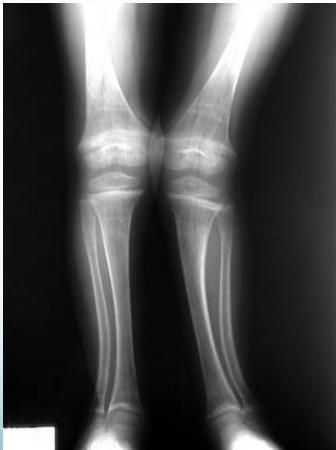

Radiological Assessment

Indications: X-ray when severe or possibly pathologic

Recommended Views:

- Standing AP film: Long film (hips to ankles) with patellae directed forwards

Radiological Parameters to Assess:

- Medial Physeal Slope

- Femoral-Tibial Axis

Conditions to Look For:

Rickets

Tibia vara (Blount’s disease)

Epiphyseal injury

Angle measurements

Medial Physeal Slope

Femoral-Tibial Axis